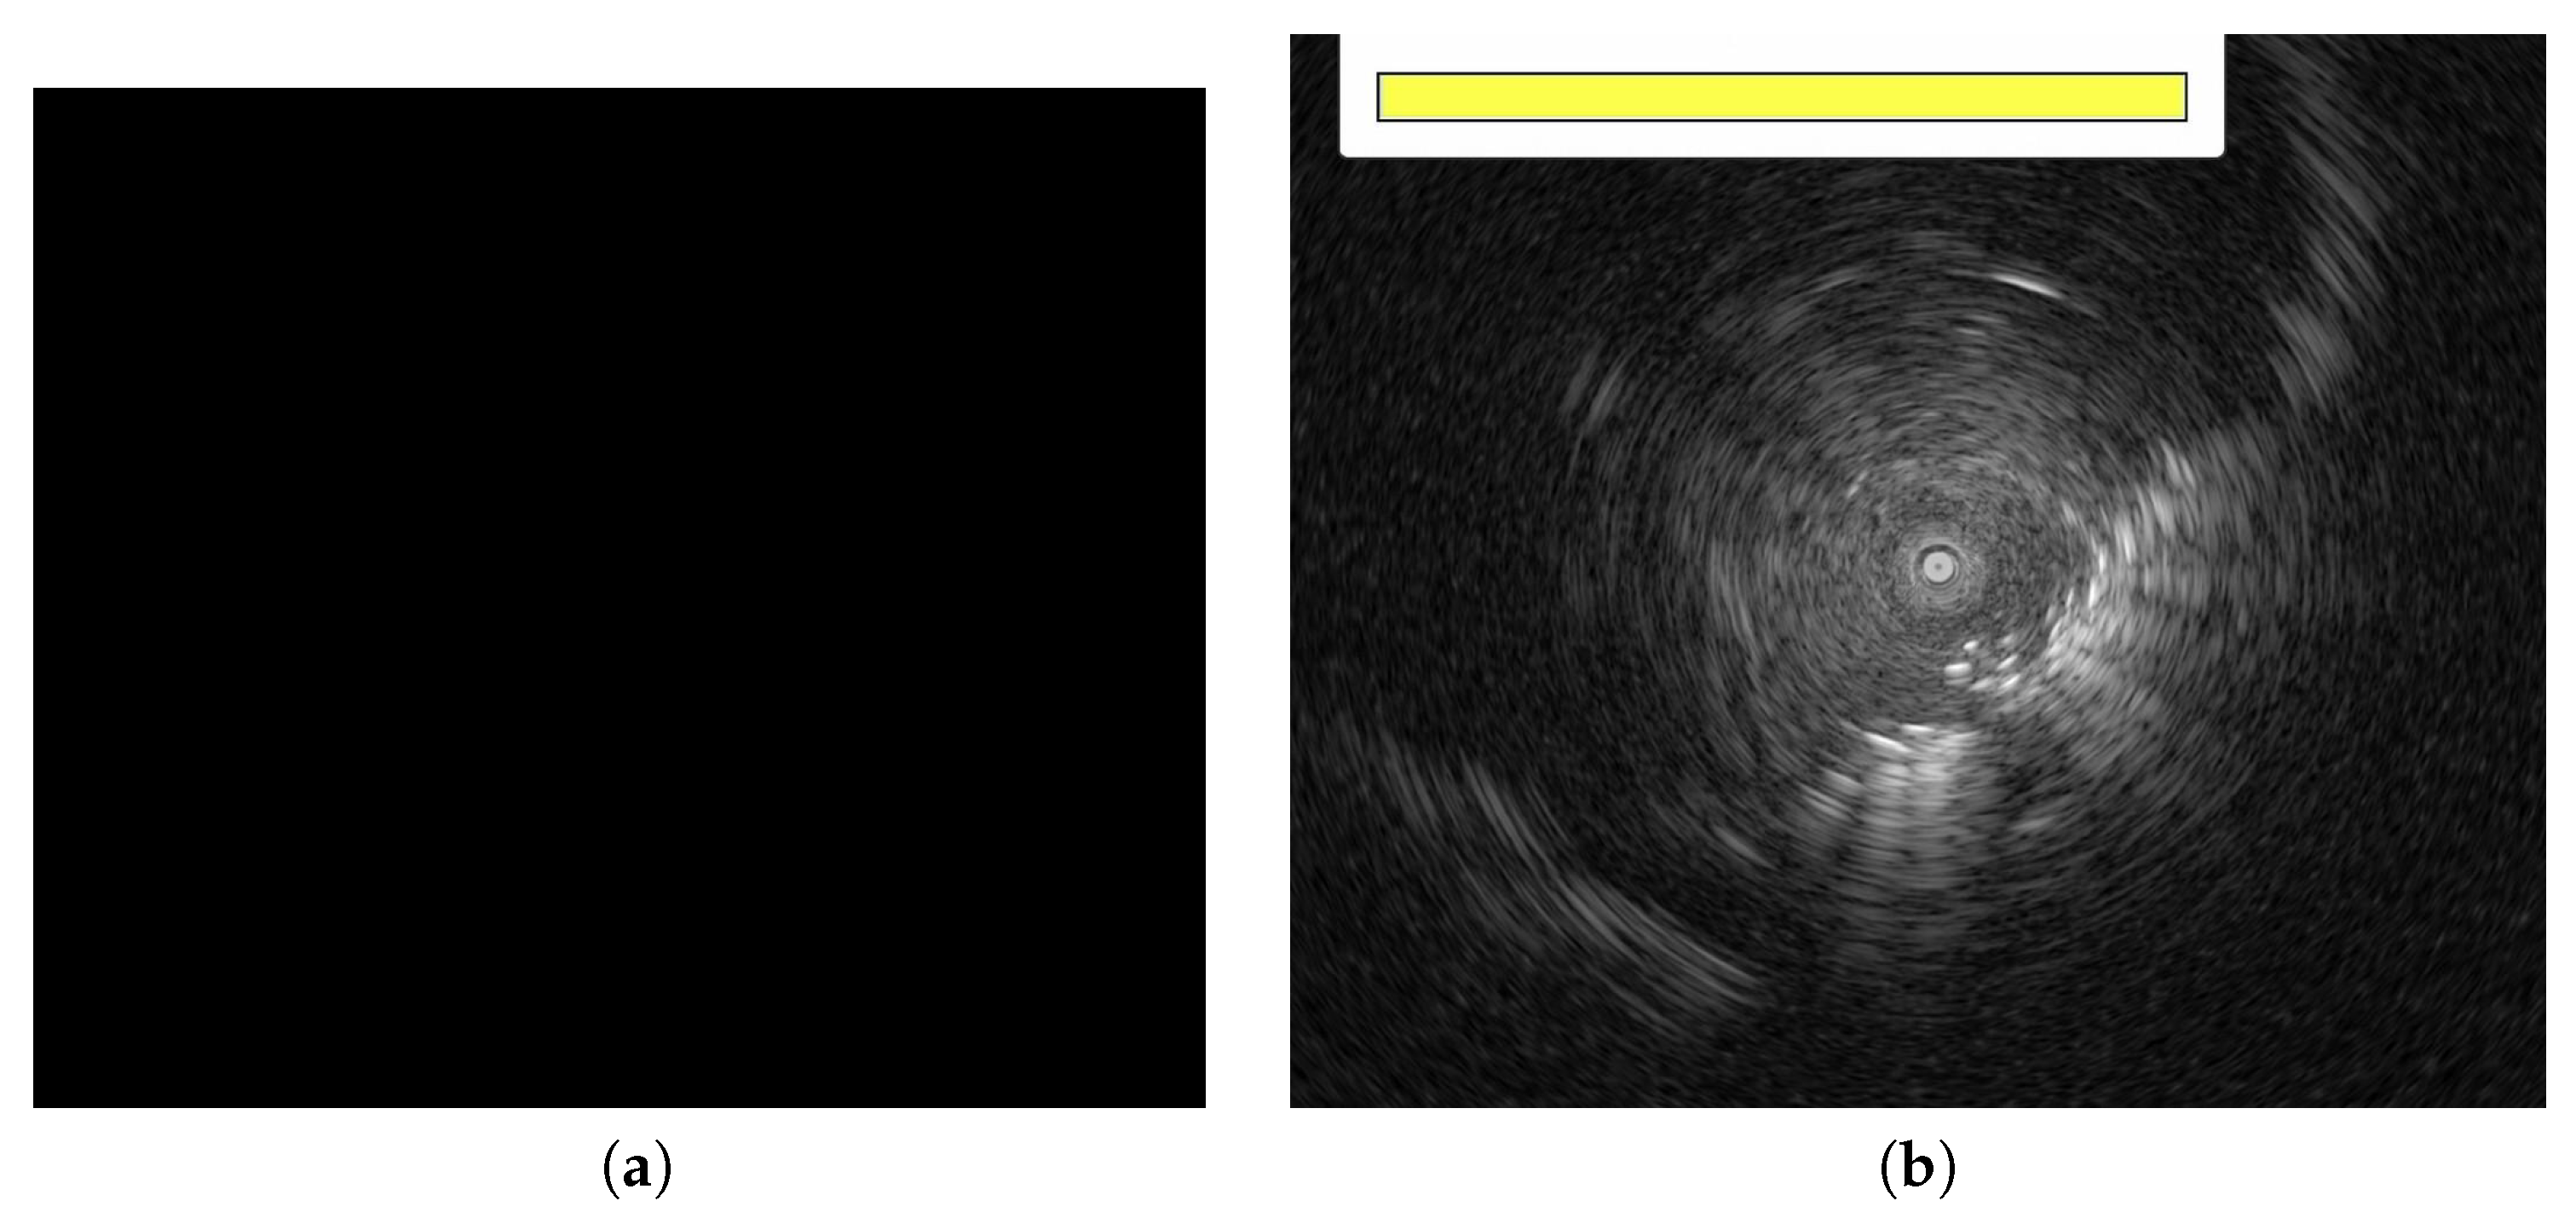

The data used in these experiments were single 940 × 940 pixel images. Therefore, data pre-processing converted EBUS video data into frame-by-frame EBUS image data for training. EBUS data pre-processing comprises six steps, organized as a flowchart in Figure 2. First, the EBUS video in MOV format was frame-by-frame converted into 1920 × 1080 pixel EBUS images (Figure 3). The image includes some text and white lines that cannot be used to train the model directly; thus, central cropping is required to remove this information. Peripheral pulmonary lesion information is primarily concentrated around the probe in these EBUS images, so the final cropped image is 940 × 940 pixels with the probe as the center. Next, the images were screened to remove images that could potentially impact the results. If there was no PPL within the image or another factor was captured, the EBUS image was excluded. Completely black images and those containing additional information, such as progress bars, were also excluded. Figure 4 shows examples of excluded EBUS images, and the data enhancement process is detailed in Section 3.2. Lastly, the enhanced data were divided into training, validation, and test sets.

Figure 4.

The examples of the EBUS image (a,b) that are screened out from the dataset.